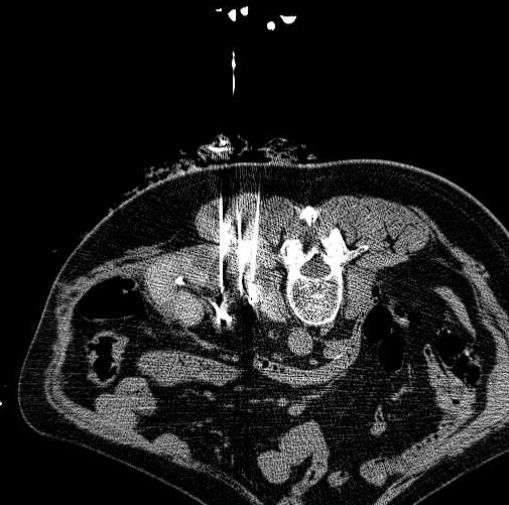

通过-140℃极冷冻结和+45℃快速复温的交替循环,在微创条件下精准杀灭肿瘤细胞,保护周围健康组织。

实时影像监测冰球范围,精确控制治疗区域,最大程度保护正常组织和重要器官